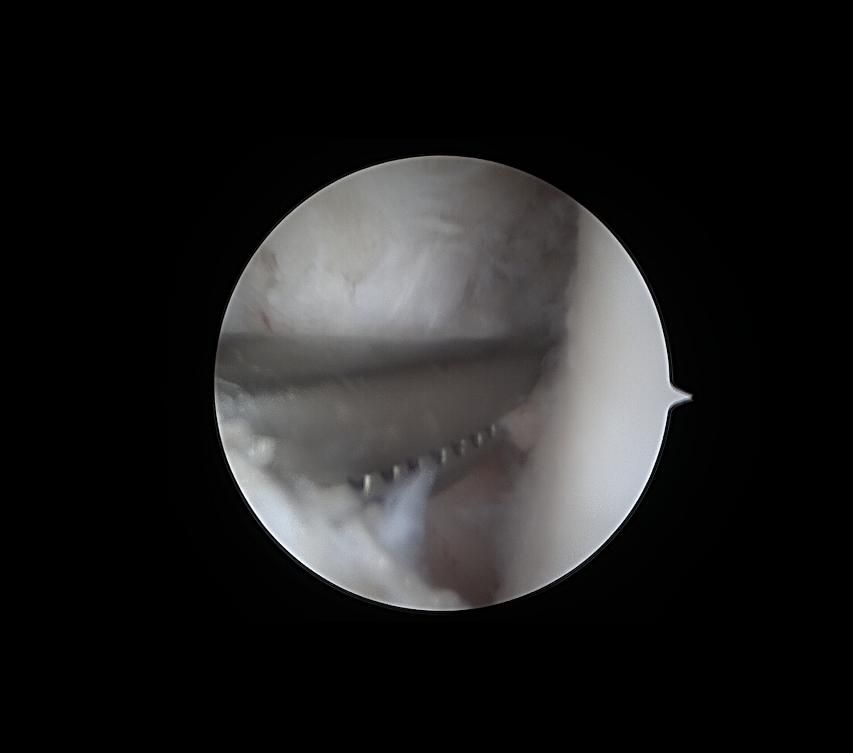

제가 발목 연골손상이라 mri와 내시경 사진이 있는데

어떤 상태인지 좀 다른 고견을 들어보고자 합니다

• 2번 째 사진

발목 연골 손상은 정도에 따라 회복 가능성 차이가 크고 mri와 내시경 소견이 매우 중요해요 완전 손상보단 부분 손상이면 재활과 치료로 걷기와 가벼운 운동은 충분히 가능할 수 있어요 이미지 확인은 병원에 내원 하셔서 정확한 진단을 받으시길 바랍니다!

현재 연골 손상이 있으신 것으로 보이는데요, 올려주신 사진이 참고에 도움이 될 수 있으나 정확한 소견을 말씀드리기에는 어려움이 있으므로 정확한 소견은 주치의에게 들어보시는 것이 좋겠습니다.